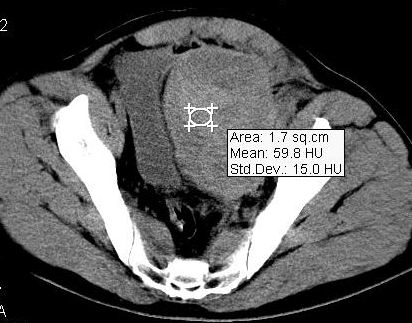

标题: CT8132:转贴:男,38岁,腹部压伤后腹痛、休克入院检查。 [打印本页]

标题: CT8132:转贴:男,38岁,腹部压伤后腹痛、休克入院检查。

结果公布:腹膜外血肿和腹腔内出血,虽然都是出血,但诊断和治疗却截然不同。如果腹腔内出血,那么在输血抗休克同时还要急诊手术止血。而腹膜外血肿不同,因为腹膜外出血往往都是小静脉丛破裂出血,手术往往找不到出血部位,找到了也很难缝合止血,造成难以控制的大出血,危机病人生命。还有腹膜对出血有个束缚作用,相当于压迫止血,利于出血自止。所以对腹膜外出血往往采取保守治疗。当然,如果腹膜外出血止不住破入腹腔,那么病人往往预后极差,恐怕连“九死一生”都谈不上。

ct上鉴别两者:腹腔内出血没有固定形态,分散在腹腔内,肠间隙等部位,破裂出血处会有较多血液聚集有血块;由于膀胱直肠陷凹是腹腔的最低处,出血和积液会积聚在此处,液体较多时膀胱会呈向前受压改变。该片血肿可见包膜(其实是腹膜)膀胱向右侧受压移位,而膀胱是腹膜间位器官。所以诊断是腹膜外血肿。